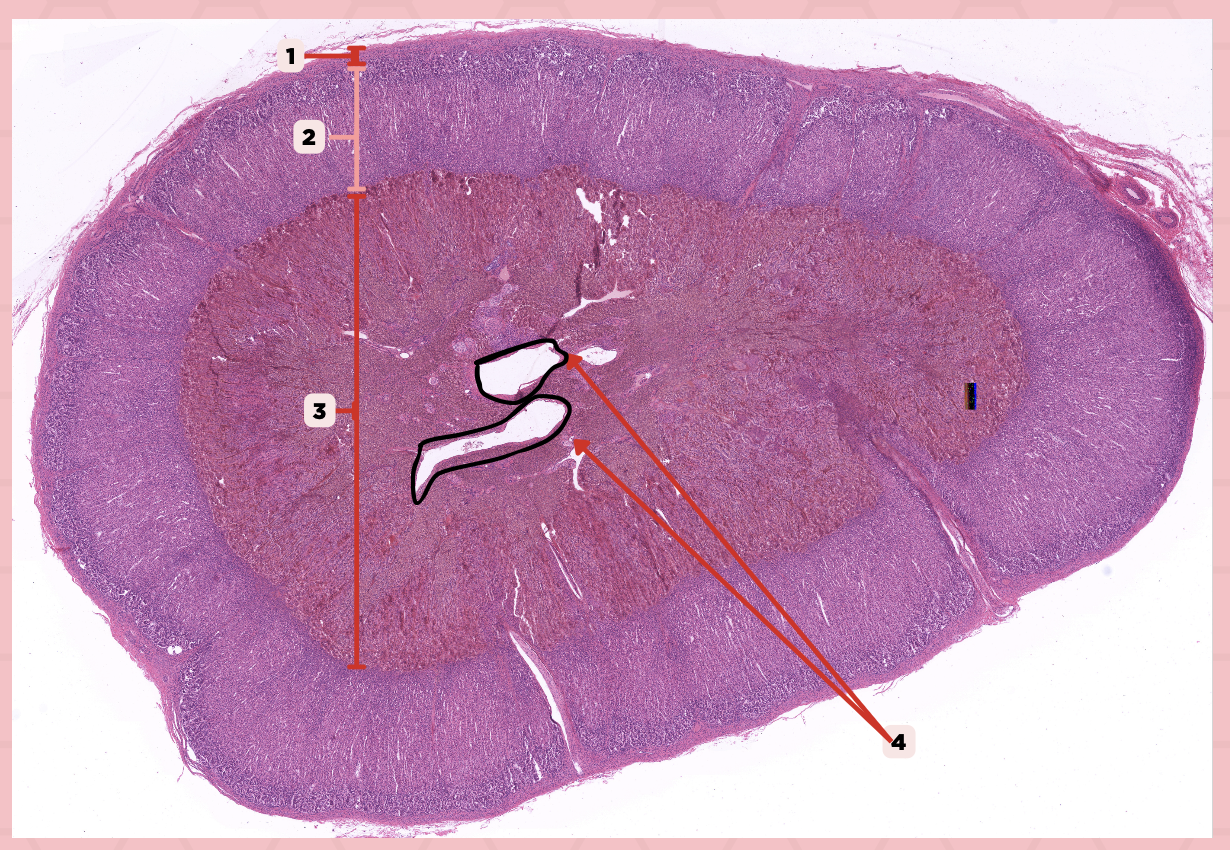

Adrenal

Identify the specimen.

Connective Tissue Capsule

Identify the structure labeled as 1.

Cortex

Identify the structure labeled as 2.

Medulla

Identify the structure labeled as 3.

Medullary Veins

Identify the structure labeled as 4.

Zone glomerulosa, Zone fasciculata, Zona reticularis

What are the zones present in pointer #2?

Catecholamines

What hormones are produced by pointer #3?